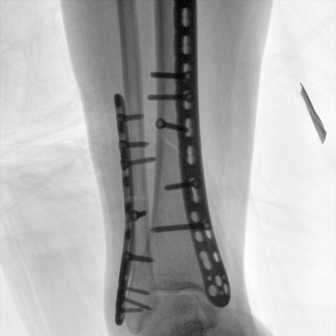

配備了兩種平板尺寸,大尺寸動(dòng)態(tài)平板探測(cè)器成像面積較傳統(tǒng)平板探測(cè)器提升了25%以上,在視野需求大的手術(shù)中,便于醫(yī)生更好定位病灶點(diǎn),規(guī)劃手術(shù)方案,減少因視野范圍不足而多次透視、點(diǎn)片造成的不便,不僅提高了手術(shù)效率,也減少了輻射劑量。